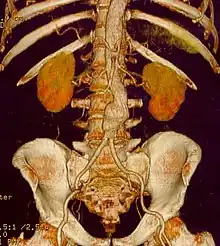

CT reconstruction image of an abdominal aortic aneurysm

The diagnosis of an abdominal aortic aneurysm can be confirmed by the use of ultrasound. Rupture may be indicated by the presence of free fluid in the abdomen. A contrast-enhanced abdominal CT scan is the best test to diagnose an AAA and guide treatment options.[10]